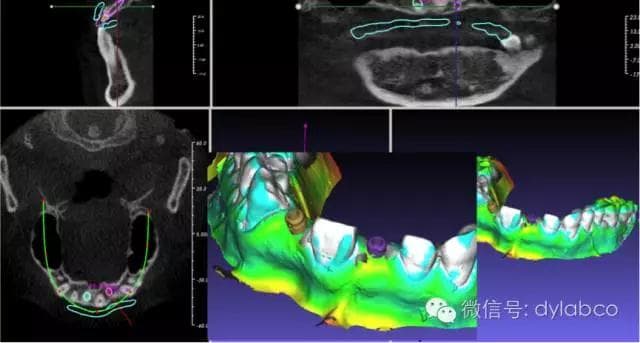

1.題目:《數字化種植導板的發展和應用》《The development and Application of Digital Implant Surgical  Guide》

摘要:報告內容包括數值化種植導板和種植設計軟件的發展,種植軟件的功能需求,國際上主要軟件的簡單回顧,軟件系統評估的主要因素,數字化種植工作流程與醫技配合,該美(GuideMia)種植設計軟件的功能介紹,特別是全口種植中的解決方案和應用,以及種植導板技術的展望。

2.主講人:高飛 博士

高飛博士:西安電子科技大學博士,美國GuideMiaTechnologies的創辦人。領導設計和開發了GuideMia 的核心技術和種植和正畸軟件。高飛博士2008-2010任美國最大的義齒公司GlidewellDental Laboratories 軟件開發部經理,負責公司在圖像處理,CADPACS等領域的軟件系統的開發。2005-2008期間,高飛在美國南加州Multi-DimensionalImaging Co.任首席軟件工程師,從事3D醫學圖像處理軟件的研究開發和應用。在此之前高飛長期擔任UGS (西門子 PLMCAD 建模系統構架組的主任軟件工程師和部門經理,領導完成了一系列UG  NX軟件項目,對大量汽車,航空航天和船舶項目有深遠影響。UGS有很多CAD/CAM業界廣為人知的技術都是在他領導下開發完成或完善的。高飛博士還是1997-1999德國洪堡學者, 1994-1996上海交通大學博士后。